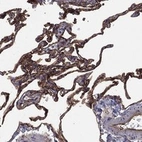

Immunohistochemical staining of human lung shows strong cytoplasmic and membranous positivity in pneumocytes.